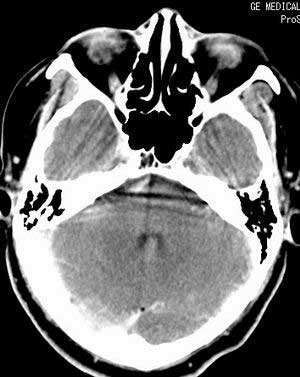

增强扫描:

脑实质密度均匀,未见异常密度灶,脑沟裂池室形态大小正常,中线结构居中.

双侧乳突蜂房密度呈气体样,慢性乳突炎可能性不大,

双侧颞叶脑实质密度均匀未见异常密度灶,

考虑颅内未见异常。

考虑耳源性脑膜炎